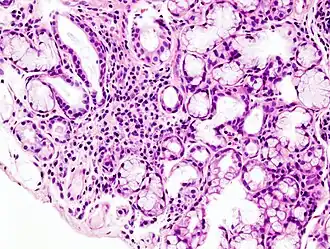

| Imagem microscópica de infiltração linfoide local numa glândula salivar menor associada à síndrome de Sjögren | |

Embora se desconheçam as causas exatas da doença, pensa-se que envolvam uma combinação de predisposição genética e um fator ambiental como exposição a um vírus ou bactéria.[3] A síndrome de Sjögren pode ocorrer de forma independente (síndrome de Sjögren primária) ou como resultado de outras doenças dos tecidos conjuntivos (síndrome de Sjögren secundária).[2] A inflamação resultante vai progressivamente danificando as glândulas.[6] O diagnóstico baseia-se numa biópsia aos tecidos e análises ao sangue para deteção de anticorpos específicos.[1] Uma biópsia positiva geralmente mostra presença de linfócitos nas glândulas.[1]